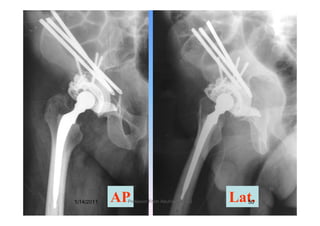

Class III 55 Y, Male, RCC

M di l ll i d d h f thMedial wall, superior dome and much of the

acetabular rim have been destroyed

(Preserved femoral head)1/14/2011 49Professor Freih AbuHassan -UJ

AP Lat.1/14/2011 50Professor Freih AbuHassan -UJ